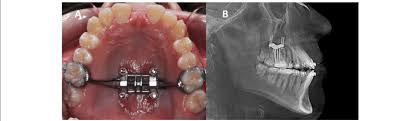

I'm gonna get braces soon

along with that im planning to get a palate expander

so will there be any noticeable changes as im just 2-3 months away from turning 20